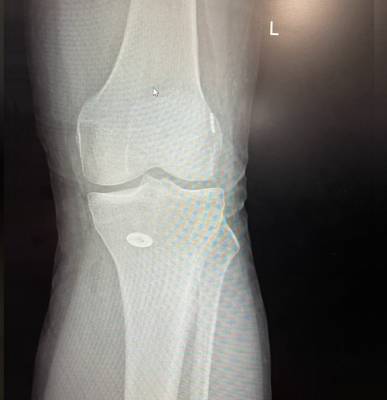

I saw Dr Haytham and his team for inflammation in my knee. His team were always friendly, professional and accommodating. Nawaz completed the physiotherapy with me and helped with the healing process, he was always very friendly and flexible with his time. Dr Haytham took great care in administering Hyleraunic Acid injections which helped with the recovery.

I had surgery with Dr. Haytham, and I’m very happy with the results. He previously operated on my leg after a fracture, and that surgery was very successful. Recently, I had another surgery on my knee, which was done in the simplest and most professional way. After the operation, I was able to return to my normal life — I can play football and be active again after a long time of not being able to. Dr. Haytham and his team took great care of me throughout the process, and I truly thank him for his excellent work and dedication